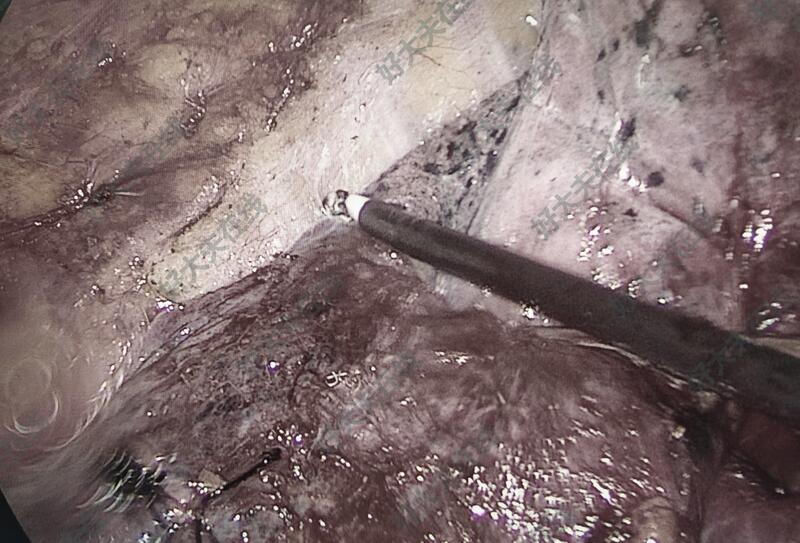

图6-10,男性,74岁,体检发现左肺上叶尖后段结节,亚实性磨玻璃样,毛刺、分叶、胸膜牵拉等,也短期随访,结节不改变,自身和子女的心里压力大(一月内反复不同医院做CT等)。胸腔镜微创手术切除,术中:整个胸膜腔完全闭锁粘连,彻底游离粘连,予以左上肺结节切除,病理报告为良性病变。

均胸腔镜微创手术切除,并送病理检查,已经出具病理报告,拔出胸腔闭式引流管,出院。并复查胸片。